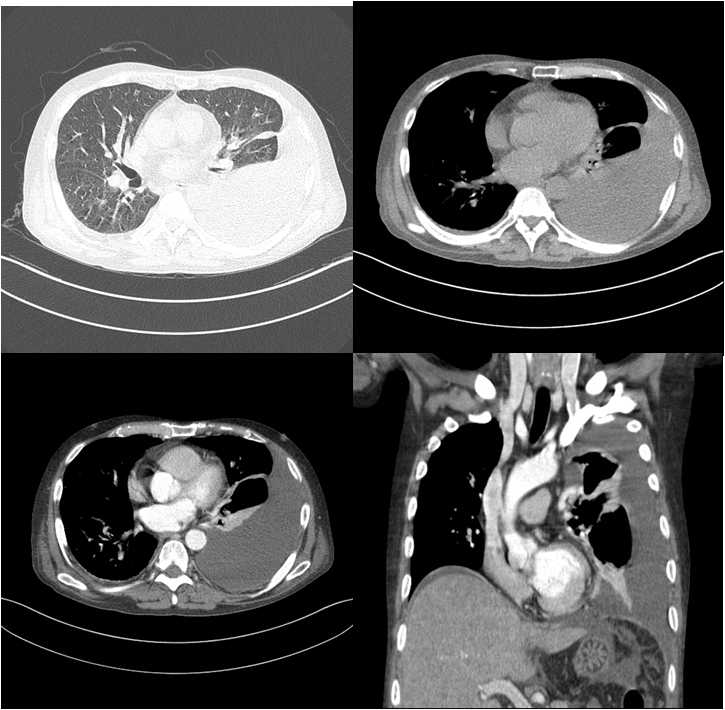

✔ 흉부 CT 검사